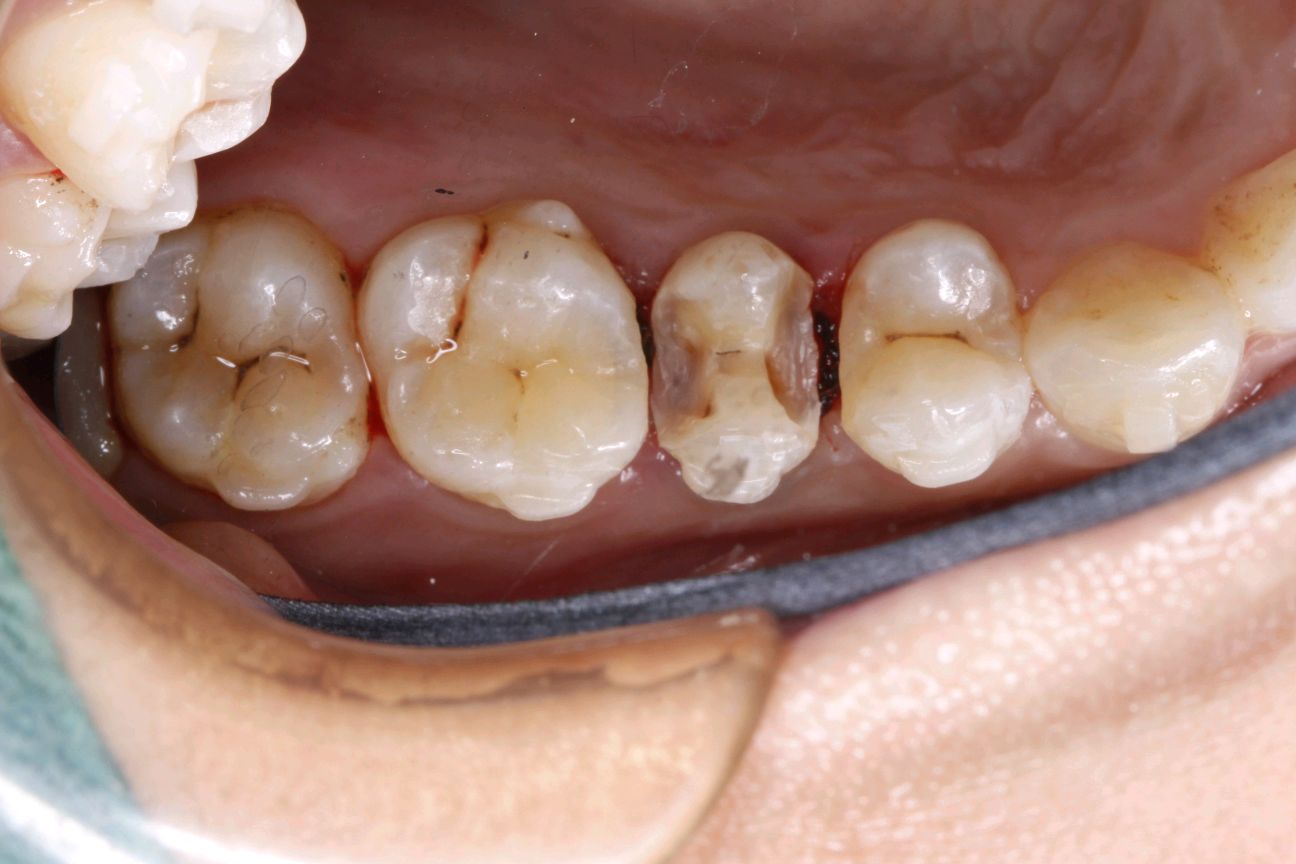

患者女,三十岁,15邻颌面大面积充填物,邻接过紧,食物嵌塞,探(+-),叩(-),冷测试正常,余无不适。很多人牙体缺损面积较大,补牙后很会出现脱落的现象,还有的让选择简单的修复模式补牙,但大量的临床研究显示,牙科树脂充填材料会产生聚合收缩(树脂材料老化),形成微渗漏,引起继发龋(顺着充填材料周围,在牙齿上出现新的腐坏、变黑)。像这种面积比较大的龋齿单纯补牙的话,不耐用。这时候就可以选择嵌体修复。嵌体牙体预备量少,能够保持牙齿外形的完整,减少对牙髓的刺激。还有就是嵌体更耐磨使用寿命较长,从而减轻了患者频繁补牙的痛苦。通过 CEREC 扫描更加精准有效的提高了我们工作效率,当天即可戴牙,正常使用。